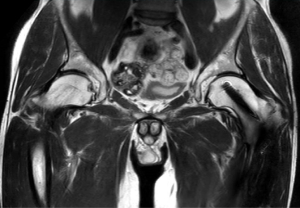

SmartSpeed は、空間分解能を最大 65% 向上させることができます¹。これにより、画像診断の精度を向上させるための情報を提供できます。

AI ベースの Philips SmartSpeed 再構成は、高速化技術の新たなベンチマークとなっています。この技術により Compressed SENSE があらゆる面で向上し、優れた画質と診断精度を維持しながらスキャン時間を短縮できます。"

Philips SmartSpeed には優れたノイズ除去機能が搭載されており、スキャン時間を延長することなく、非常に高分解能のイメージングを実現できます。これは、血管系の小さな病変を描出する場合などに非常に重要です。"